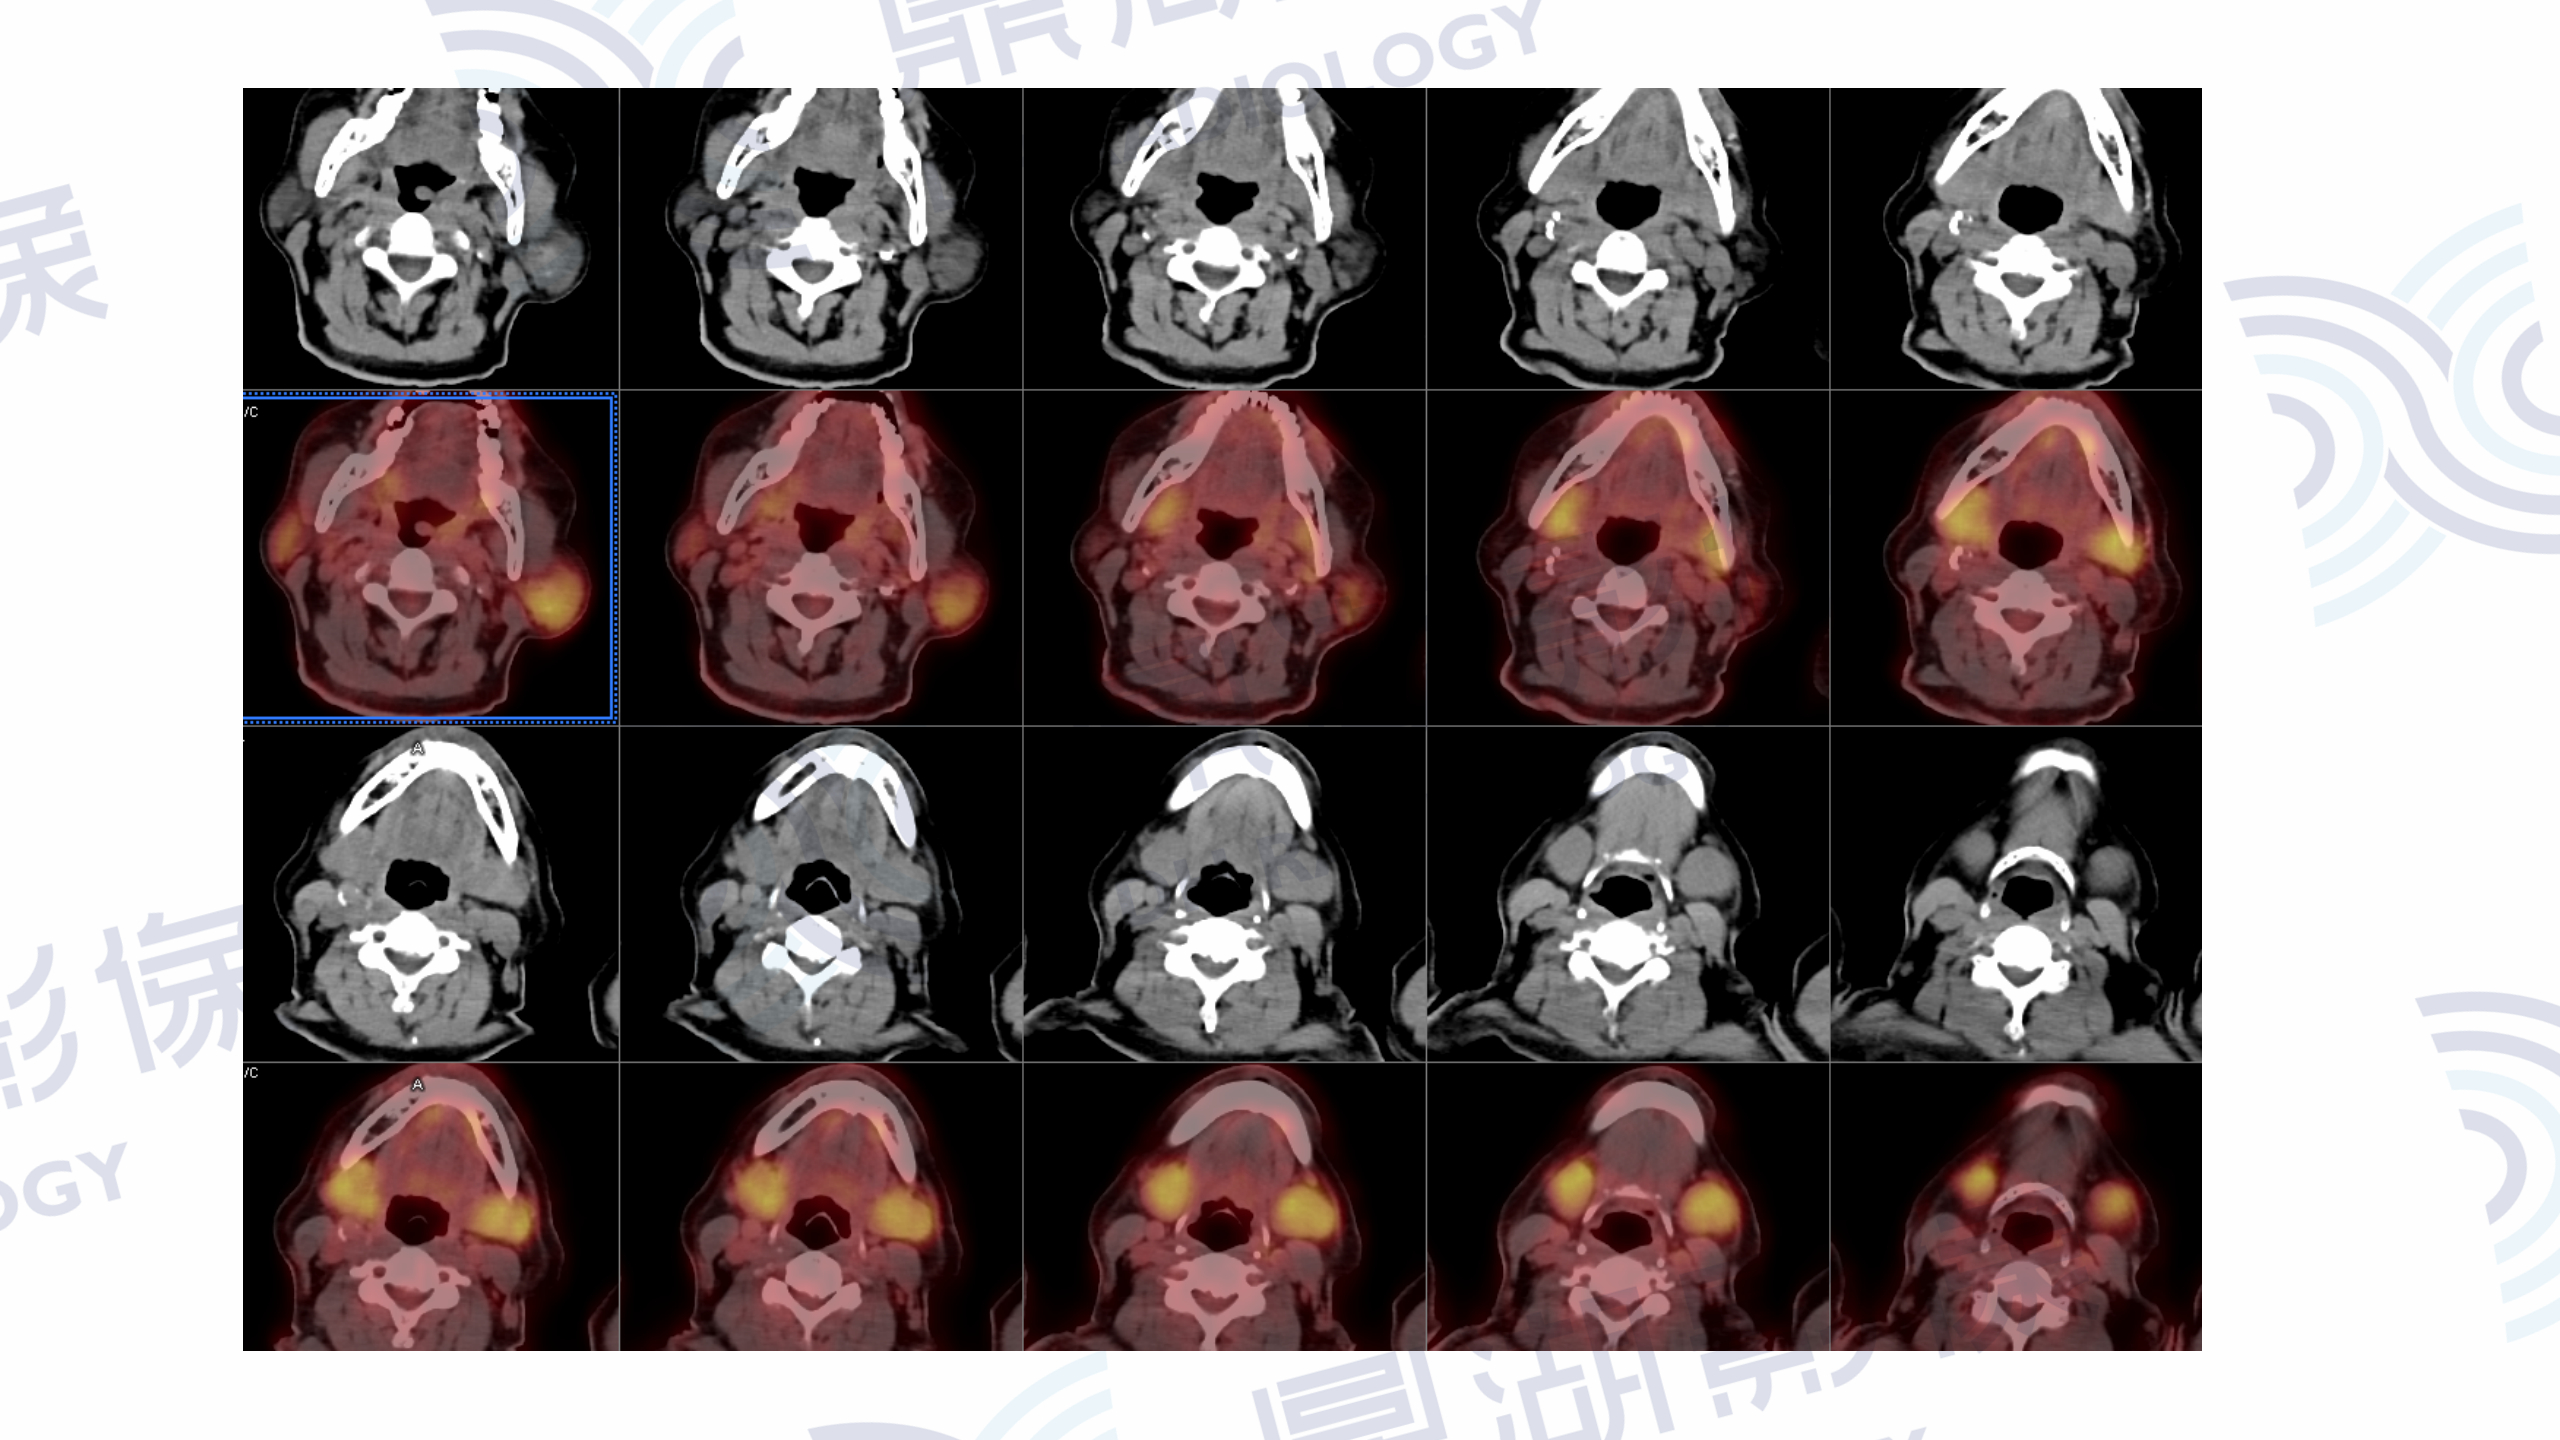

PET/CT提示:口咽左侧壁至左侧声门上软组织肿块,FDG摄取增高,SUVmax=13.1。